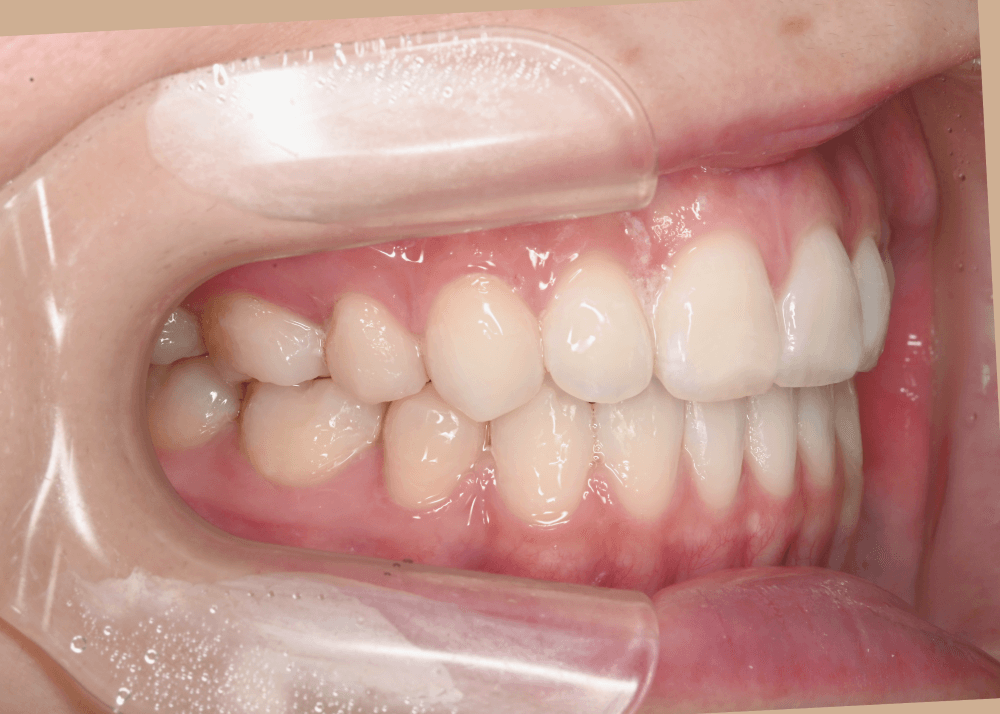

まとめ・治療後の変化

治療後は、気にされていた「口ゴボ(口元の突出感)」が改善され、自然でバランスの良い口元になりました。

隙間のあった前歯も、しっかり噛み合うようになっています。

治療後(32か月)